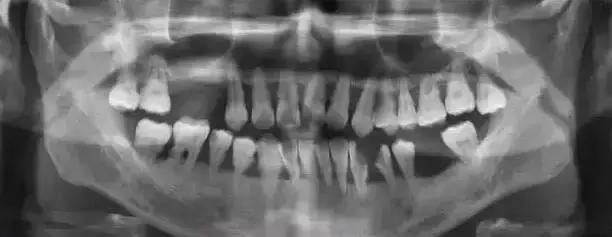

临床表现

我们了解到牙周炎的外部表现,如口臭、牙龈出血、牙龈萎缩等,具体就不多做介绍。临床上,可见龈缘、龈乳头和附着龈的肿胀、质松软,呈深红色或暗红色,探诊易出血。随着炎症的进一步扩散,还出现下列症状:

1.牙周袋形成:由于炎症的扩展,牙周膜被破坏,牙槽骨逐渐吸收,牙龈与牙根分离,使龈沟加深而形成牙周袋。可用探针测牙周袋深度。

3.牙齿松动:由于牙周组织被破坏,特别是牙槽骨吸收加重时,支持牙齿力量不足,出现牙齿松动、移位等现象。此时患者常感咬合无力、钝痛,牙龈出血和口臭加重。